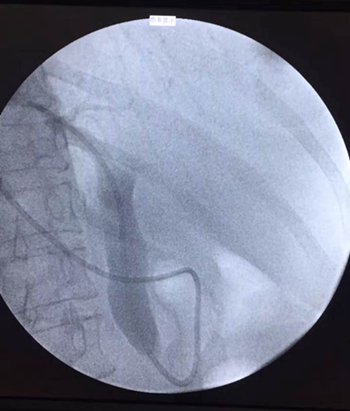

近日,陇南市人民医院消化内科运用ERCP治疗胰胆疾病的微创术成功完成一例十二指肠镜逆行胰胆管造影(ERCP)术+内镜下鼻胆管引流(ENBD)术。该项技术的成功开展,填补了我院在ERCP微创治疗方面的空白。

患者因“上腹疼痛不适1月,加重伴恶心、呕吐1天”入院,入院后行上腹部B超示:胆囊体径增大、腔内结石,肝外胆管扩张。考虑到传统手术治疗胆总管结石对患者伤害较大,为了更加安全高效,陈洮明副院长和主治医师刘健对患者病情进行了详细评估,经过缜密的术前讨论后,建议行ERCP+ENBD术治疗。

4月2日,科室使用医院最新引进的全新高清电子十二指肠镜为患者手术,在陈洮明副院长的指导下,主治医师刘健操作, 护士王秀英、党海珍协作,并在放射科的大力支持下行ERCP+ENBD术,手术过程非常顺利,术后患者未诉特殊不适,术后经常规抑酸、抗感染等治疗后,患者症状明显好转。

经内镜逆行胰胆管造影是将纤维十二指肠镜插至十二指肠降部,找到十二指肠大乳头(下简称乳头),由活检管道内插入塑料导管至乳头开口部,注入造影剂后x线摄片,以显示胰胆管。本法于1968年由mccunne氏首先报导,后由大井等人使本法日趋完善,近十年来,随着器械及插管技术的不断进步,ercp成功率逐年提高,目前已达90%左右,成为诊断胰腺和胆道疾病的重要手段。